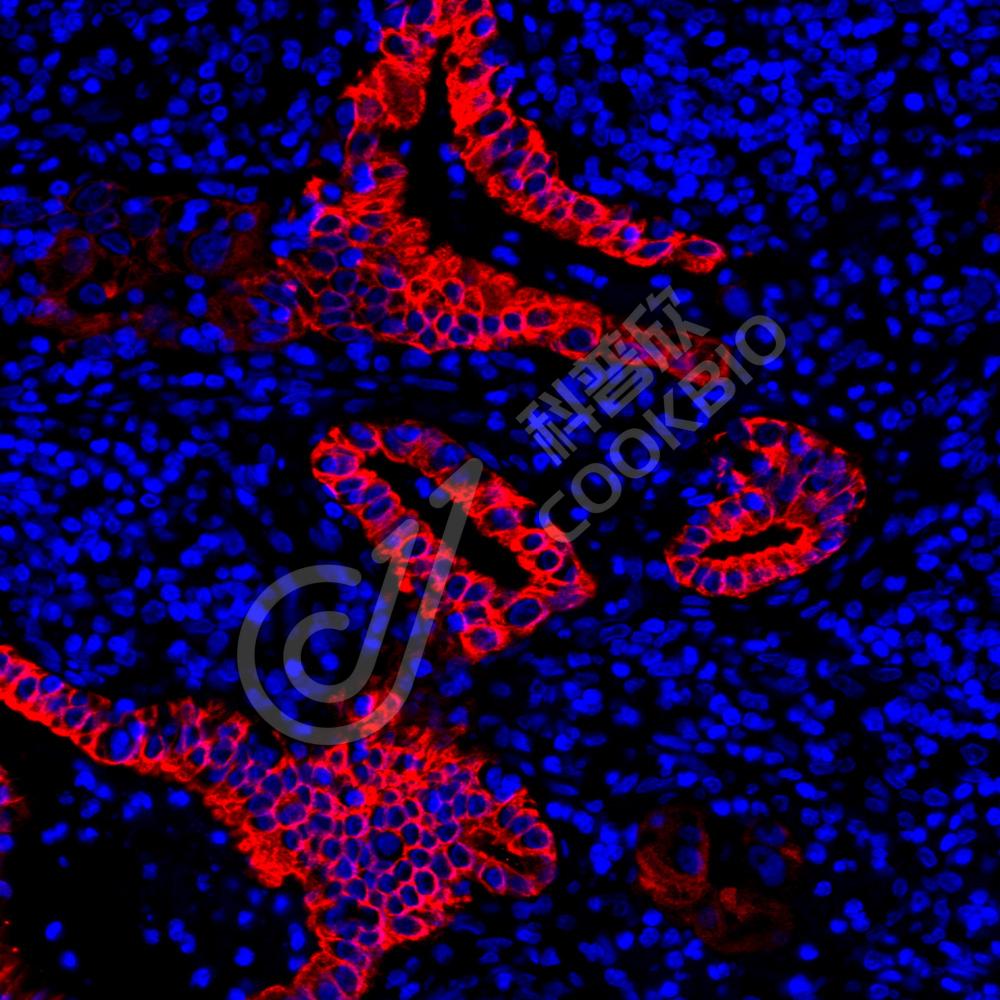

IF检测Cytokeratin 5蛋白(货号 K1333738)(红色).

样品: 人卵巢癌, 4%多聚甲醛 (货号KSG1101) 固定12-24小时.

抗原修复: Tris-EDTA抗原修复液(pH 9.0) (KSG1203), 98℃, 20分钟.

封闭: 3% BSA(货号KSGC305010)的PBS溶液, 室温孵育30分钟.

—抗: 1: 2000稀释, 4℃ 孵育过夜.

二抗: Cy3标记山羊抗兔IgG (H+L) (货号KB63909), 1: 300稀释, 室温孵育1小时.